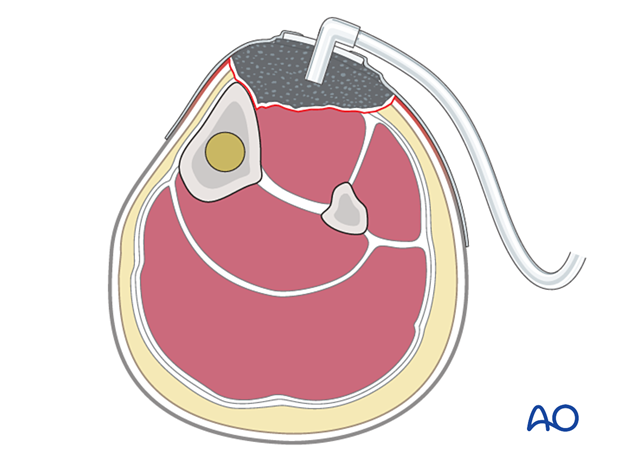

All open wounds need to be protected from secondary contamination. A sealed dressing (eg, an antibiotic bead pouch, or vacuum-assisted closure device (VAC)) can be used. VACs help to reduce the size of an open wound and promote the formation of granulation tissue. This device may permit early split-thickness skin graft closure.